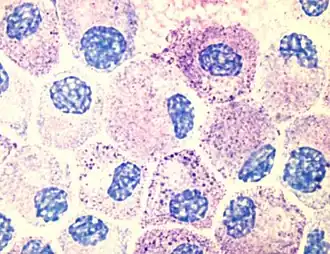

Mestcellen[1] of mastocyten[1] zijn gespecialiseerde cellen die zich bevinden in weefsels die in contact staan met de buitenwereld. Ze spelen een rol bij de immuunrespons. Ze werden eerst beschreven door Paul Ehrlich in 1878 vanwege hun kleuringseigenschappen en grote korrels (granula) in het cytoplasma.

Als een antigeen door meer dan 1 IgE molecuul wordt 'gepakt' (dit heet cross-linken) vindt degranulatie plaats: de granula (hierboven korrels genoemd), die eigenlijk pakketjes met mediatoren zijn, migreren naar de celmembraan en storten hun inhoud door exocytose buiten de cel uit, waarbij stoffen zoals histamine vrijkomen en lokaal de immuunrespons versterken door andere cellen van het immuunsysteem vanuit het bloed naar de lokale infectie te brengen door de bloedvatdoorlaatbaarheid te vergroten.

Mestcellen lijken sterk op basofiele granulocyten (een type witte bloedcellen).